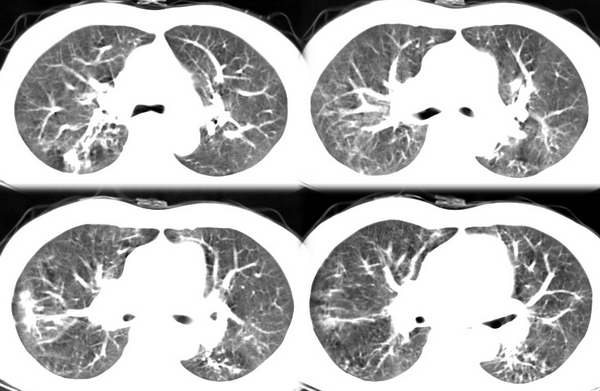

咳嗽6月低热1月!

右上叶背段及左下叶见斑片状密度不均模糊影,右中叶支气管狭窄,中叶密度增高,体积缩小.纵隔未见明确淋巴结.结论:1、两俩结核,右中叶支气管内膜结核,并中叶肺不张。2、两肺炎;右中心型肺癌,并阻塞性肺不张。

右肺上叶尖后段及左肺舌叶 下叶见斑片状密度不均模糊影,右中叶支气管狭窄,中叶密度增高,体积缩小.纵隔未见明确淋巴结。考虑:双肺结核伴右侧中叶不张。

右上叶背段及左下叶见斑片状密度不均模糊影,右中叶支气管狭窄,近端未见肿块,中叶密度增高,体积缩小.纵隔未见明确淋巴结.结论:两肺结核,右中叶支气管内膜结核,并中叶肺不张。肺纹理粗乱,有慢支表现,伴有感染存在。

1.右下叶背段结核。2.支气管炎伴双下肺感染。3.右中叶内侧段肺不张。至于原因,考虑支气管内膜结核,建议纤支镜检查。

ct显示病灶呈多灶性分布,主要分布在双肺上叶后段,右肺中叶及左肺下叶,右肺上病灶内可见点状钙化,纵隔内示淋巴结钙化,结合病史6个月伴低热,考虑感染性病变,结核可能大.

右上叶及左下叶多发结节状、斑片状阴影。右中叶不张。支持肺结核并右中叶不张。